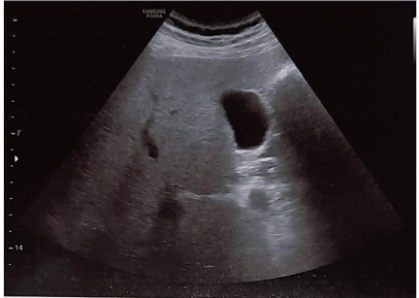

A 35-years-old non-smoker, non-alcoholic, non-vegetarian, menstruating female presented with moderate to severe spasmodic pain in right upper abdomen and epigastric region for one year. Pain was aggravated after the fatty and spicy meal. There was history of several episodes of vomiting during attack of severe pain in last three month which occurred typically in night after 2-3hours of heavy meal. Vomiting was bilious in nature. She took antacids, H2 blockers, proton pump inhibitors and antiemetic along with pain killers but could not be improved. She had a history of hospital admission for once six months before. The patient was referred to us for the laparoscopic cholecystectomy. The patient was then thoroughly examined and nothing significant could be detected in systemic but on local examination, hepatomegaly was found with palpable gallbladder. Ultrasonography (USG) abdomen Figure 4 showed large over-distended gallbladder with mild wall thickness and thick sludge and concretions in the lumen. The blood biochemistry revealed high total leukocyte counts (14800/cumm) with neutrophilia (82%). Serology showed raised Alkaline phosphatase (325 U/L), Aspartate transaminase (AST) 89 IU/L and Alanine aminotransferase (ALT) 142 IU/L. Rest of the lab parameters were within normal limits. Patient was given OmlivTM, one tablet twice daily along with broad-spectrum antibiotics and PPIs. Antibiotics and PPIs were stopped after 7days when TLC became normal (7300/cumm) and the OmlivTM, one tablet twice daily continued for the complete 45 days therapy. The follow-up USG (Figure 5) revealed normally distended gallbladder with normal wall thickness and clear lumen. There was no evidence of sludge or concretions in the gallbladder lumen. Blood biochemistry and abnormal liver function tests also come within normal limits.

Figure 4 Case No. 2 [Pre-treatment ultrasonography scan showing biliary sludge & concretions].